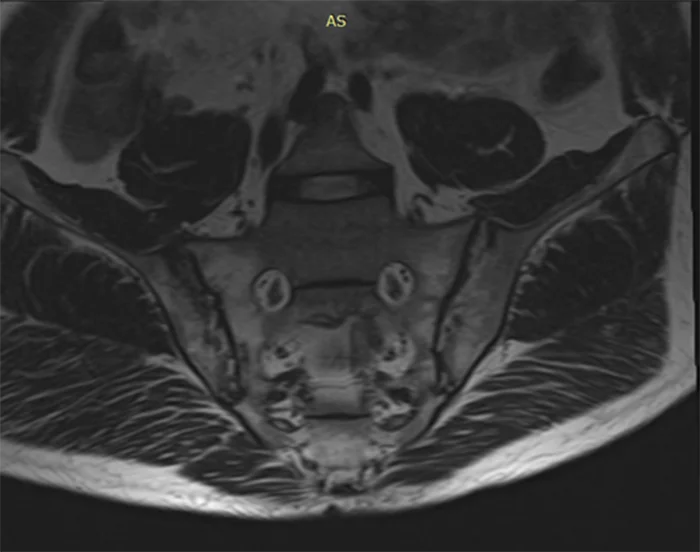

Це МРТ дослідження показує крижово-клубові суглоби, які з’єднують центральну крижову кістку з клубовими кістками таза з кожного боку. МРТ крижово-клубового суглоба – неінвазивна процедура, яка допомагає діагностувати захворювання, пов’язані з основою хребта.

МРТ крижово-клубових суглобів є незамінним методом обстеження для виявлення запальних змін крижово-клубового зчленування. Завдяки використанню спеціальних послідовностей з придушенням сигналу від жирової тканини (STIR), значно зростає чутливість методу до виявлення збільшення вмісту рідини в тканинах (набряку і запалення). Що дозволяє діагностувати сакроілеіт на дорентгенологіческіх стадіях.

- Найвідомішим типом запального артриту є анкілозуючий спондиліт (хвороба Бехтерєва), який вражає переважно хребет, а також крижово-клубові суглоби. Симптоми анкілозуючого спондиліту включають біль і скутість, які не зменшуються під час відпочинку, але посилюються під час фізичних вправ, біль у сідницях і біль у попереку серед ночі. Він починається набагато раніше, ніж остеоартрит, і симптоми починаються у людей у віці двадцяти років або раніше. На пізніх стадіях захворювання нова кістка росте між хребцями, тому вони ефективно зростаються, викликаючи біль і обмеження рухів.